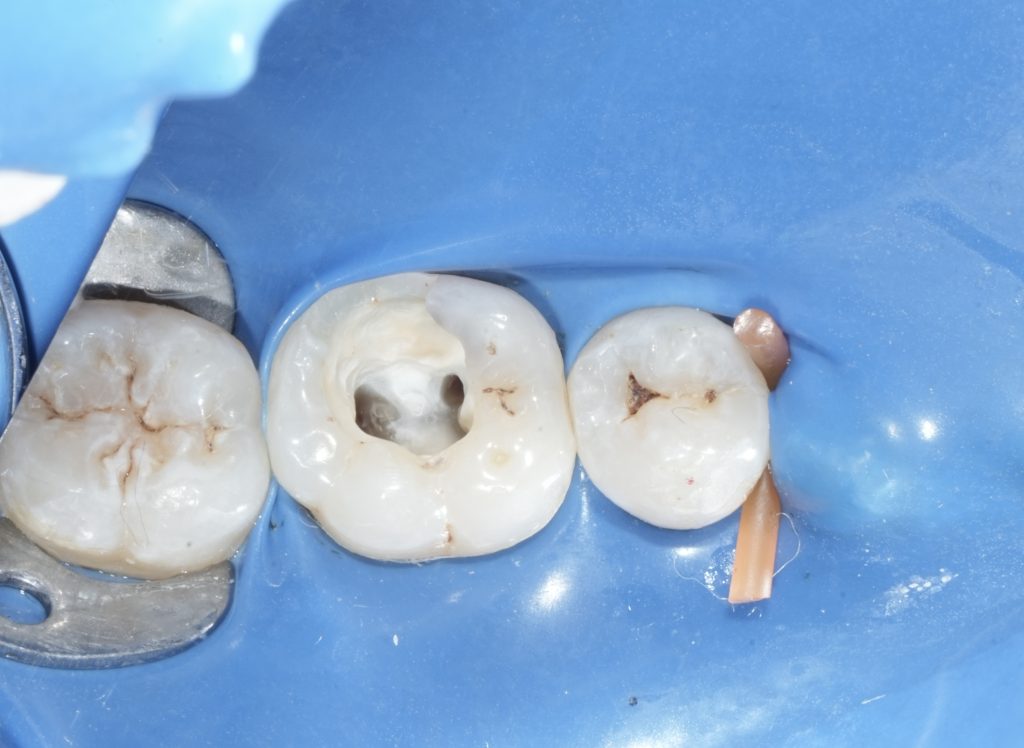

Case Assessment and Diagnosis

Clinical examination revealed a deeply carious mandibular first molar with pulpal involvement. Radiographic evaluation showed intact periapical structures and favorable root morphology. The tooth was deemed restorable with adequate remaining enamel and dentin, making it suitable for a bonded restorative approach following endodontic therapy.

Isolation and Access

Rubber dam isolation was established to eliminate salivary contamination and enhance procedural accuracy. Access cavity preparation was performed under magnification, prioritizing preservation of pericervical dentin. Canal orifices were located conservatively to maintain structural integrity.